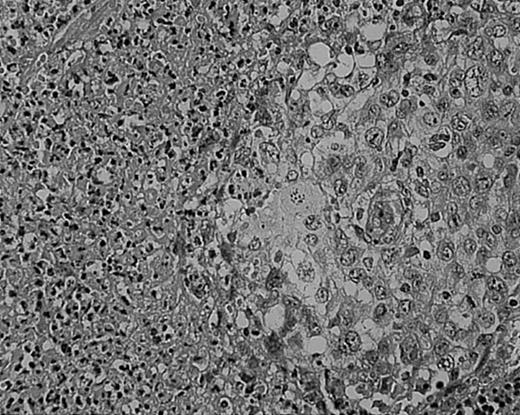

As we have previously reported, tissue eosinophilia is the strongest prognostic indicator in NS.19 Eosinophilia was not included in the BNLI criteria. We therefore propose a new grading system that includes this important risk factor and should be easier to use than the BNLI criteria. The 3 criteria of the new grading system are: eosinophilia (approximately > 5% of all cells or clusters in at least 5 high-power fields; new feature; Figure5); lymphocyte depletion (< 33% of all cells in the whole section; simplified feature of BNLI; Figure6); and atypia (> 25% of H/RS cells bizarre and highly anaplastic appearing, with pleomorphic nuclear features, hyperchromatism, and highly irregular nuclear outlines; simplified feature of BNLI; Figure 7). Cases showing none of these factors are called NS-low risk (NS-LR) and each case showing one or more of the factors is called NS-high risk (NS-HR).

Lymphocyte depletion in NS HD.

This example shows lymphocytes in less than 33% of all cells. Stained with H&E. Original magnification, × 400.